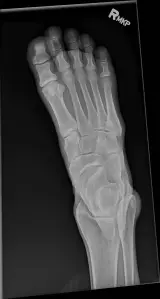

MSK Radiographs